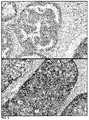

FIG.7 are IHC assay images depicting some embodiments of a negative (top) and positive (bottom) staining result for FOXA1.